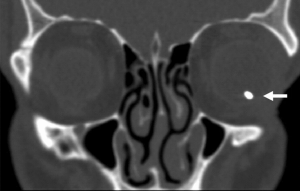

Please see the separate page on IOFB for full details on imaging and evaluation of IOFB. In terms of diagnosis of siderosis, if there is a high clinical suspicion for siderosis and no previously known IOFB, computed tomography (CT) serves as the gold standard for detecting metallic IOFBs. Ultrasound may be useful for evaluating associated pathology, while magnetic resonance imaging (MRI) is contraindicated when ferromagnetic material is suspected.